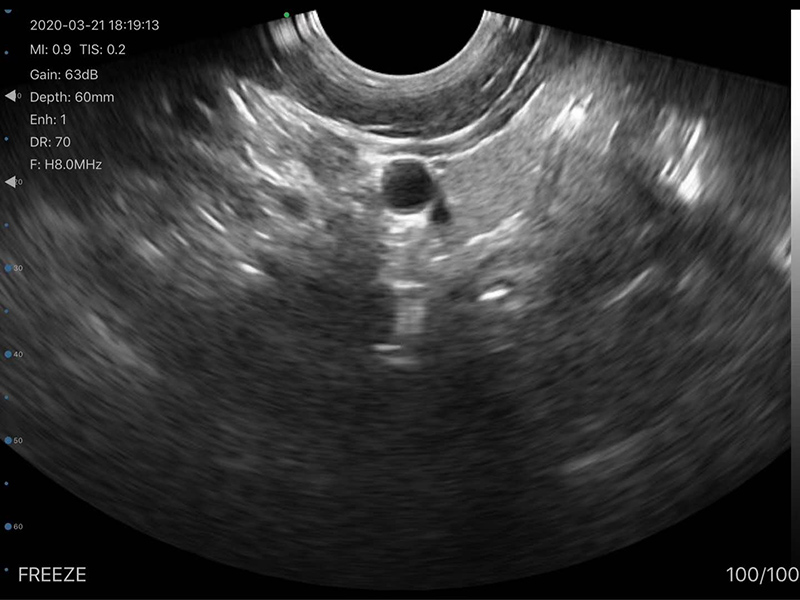

• 探头频率:凸阵3.2/5.0MHz,腔内6.0/8.0 MHz

• 扫描声头:同时具备凸阵、腔内两个声头,并可通过按键快速切换

• 扫描深度:凸阵90/160/220/305mm,腔内 30/60/90/120mm,可调

• 扫描角度和宽度:凸阵R60,腔内R13